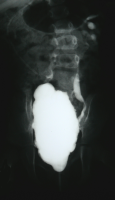

Bei einem 8-jährigen Mädchen mit MMC, ventriculo-peritonealem Shunt und rezidivierenden Harnwegsinfekten ergab die urologische Untersuchung mit Sonographie, AUR, MCU und Urodynamik einen Harnstau II. Grades der linken Niere mit Verplumpung des NBKS (AUR), glatte Abflussverhältnisse rechts (Abbildung 15), VUR links (Abbildung 16b).

Ein VUR war nicht mehr nachweisbar (Abbildung 17ab).